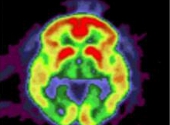

În imaginea de mai sus (realizată cu ajutorul unui tomograf cu pozitroni) a creierului se pot vedea depozitele de amiloid (cele mai mari au culorile galben şi roşu) din creierul unui pacient ce suferă de Alzheimer. Fotografia a fost realizată la Centrul Knight de Cercetare a Alzheimerului.